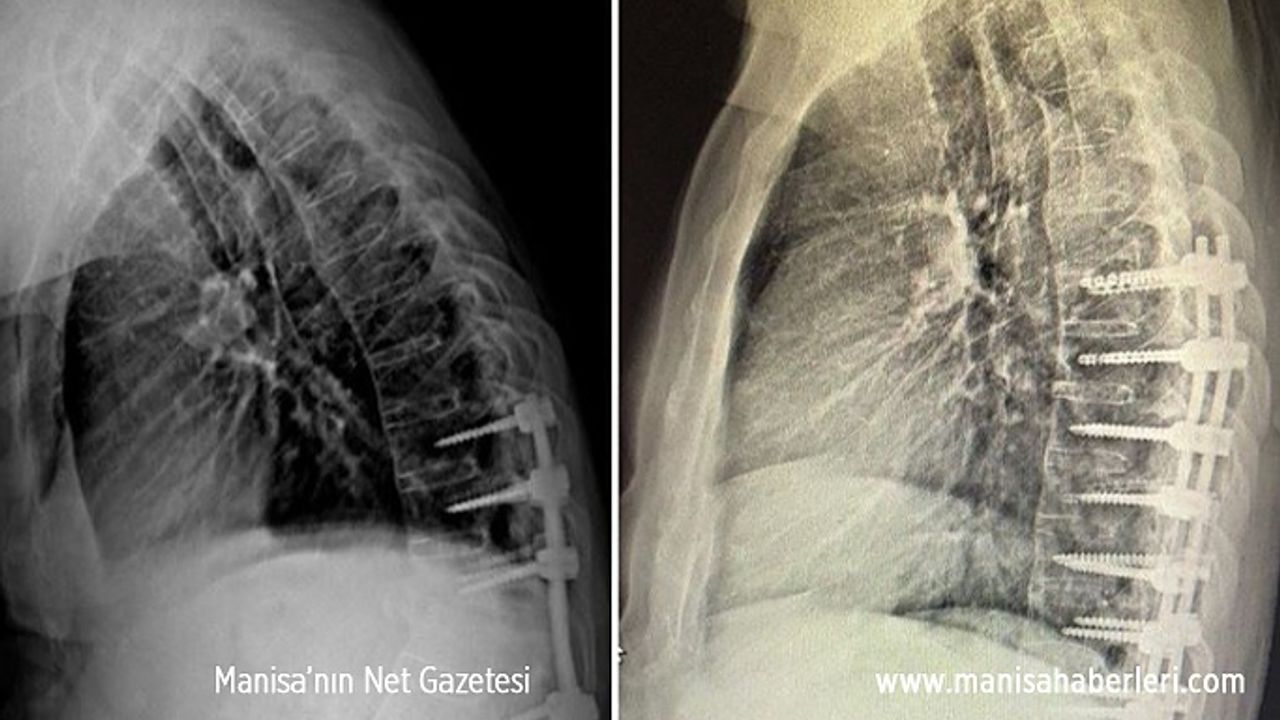

Manisa Şehir Hastanesi Beyin ve Sinir Cerrahi Kliniğinde skolyoz ve kifoz ameliyatları başarı ile gerçekleştirilmeye başladı. Manisa’da M.E. (63) isimli yaşlı adam 6 ay önce geçirdiği trafik kazası sonrası omurgasında oluşan kırıklar nedeniyle başka bir şehirde ameliyat oldu. Aradan geçen 6 ay içinde yaşlı adamın omurgasında öne doğru kamburluk, solunum sıkıntısı ve yürüme bozukluğu başladı. Manisa Şehir Hastanesine müracaat eden yaşlı adam yapılan tetkiklerin ardından Beyin ve Sinir Cerrahi Hekimi Op. Dr. Ülkün Ünlü Ünsal tarafından ankilozan spondilit tanısı ile ameliyata alındı. Yapılan başarılı operasyonun ardından yaşlı adamın hem kamburluğu giderildi hem de yeniden sağlığına kavuştu.

Ameliyat hakkında bilgi veren Manisa Şehir Hastanesi Beyin ve Sinir Cerrahi Hekimi Op. Dr. Ülkün Ünlü Ünsal, “M.E. 63 yaşında ve halk arasında Ahmet Mete Işıkara Hastalığı olarak da bilinen Ankilozan Spondilit tanılı hastamız, 6 ay önce geçirmiş olduğu trafik kazası sonrası omurgasında T12-L1 kırık oluşmuş ve dış merkezde ameliyatı gerçekleştirilmiş. Aylar içinde omurgasında öne doğru oluşan kamburluk (kifoz) meydana gelmiş. Omurgasındaki eğrilik nedeni ile duruş bozukluğuna bağlı solunum sıkıntısı ve yürüme bozukluğu yaşamaya başlayan hasta M.E. Manisa Şehir Hastanesi Beyin ve Sinir Cerrahi Kliniğine başvurmuş gerekli tetkikleri yapılmış, gerçekleştirilen başarılı ameliyat sonucunda omurgasındaki eğrilik giderilerek sağlığına kavuşmuştur. Hastanemizde cerrahi tedavi olarak omurga tespit sistemleri ve ameliyatları ücretsiz olarak yapılmaktadır” dedi.